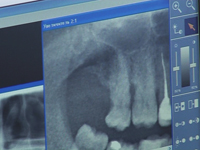

В нашей клинике работает современный рентгенодиагностический кабинет, который оснащен цифровыми рентгеновскими аппаратами последнего поколения немецкой фирмы Sirona (фото1, 2). Аппарат визиограф позволяет сделать снимок отдельного зуба в считанные секунды. Для этого достаточно разместить внутриротовую камеру в полости рта возле нужного зуба и изображение исследуемого зуба и его корневой системы появится на экране (фото 3, 4, 5). Аппарат ортопантомограф показывает на экране монитора все зубы и их корневую систему, что дает врачу возможность выявить все заболевания зубов и полости рта. (фото 6, 7, 8). Программа обработки изображения дает возможность на экране монитора увеличивать или уменьшать изображение зубов, регулировать яркость и контрастность изображения. (фото 9, 10, 11). В интересах безопасности пациентов и обслуживающего персонала проводятся регулярные работы по осмотру и техническому обслуживанию аппаратуры. Для пациентов и обслуживающего персонала имеются в достаточном количестве средства защиты от ионизирующих излучений: фартуки, рентгенозащитные резино-свинцовые ширмы. (фото 12). |

| Фото 9 | Фото 10 | Фото 11 | Фото 12 |